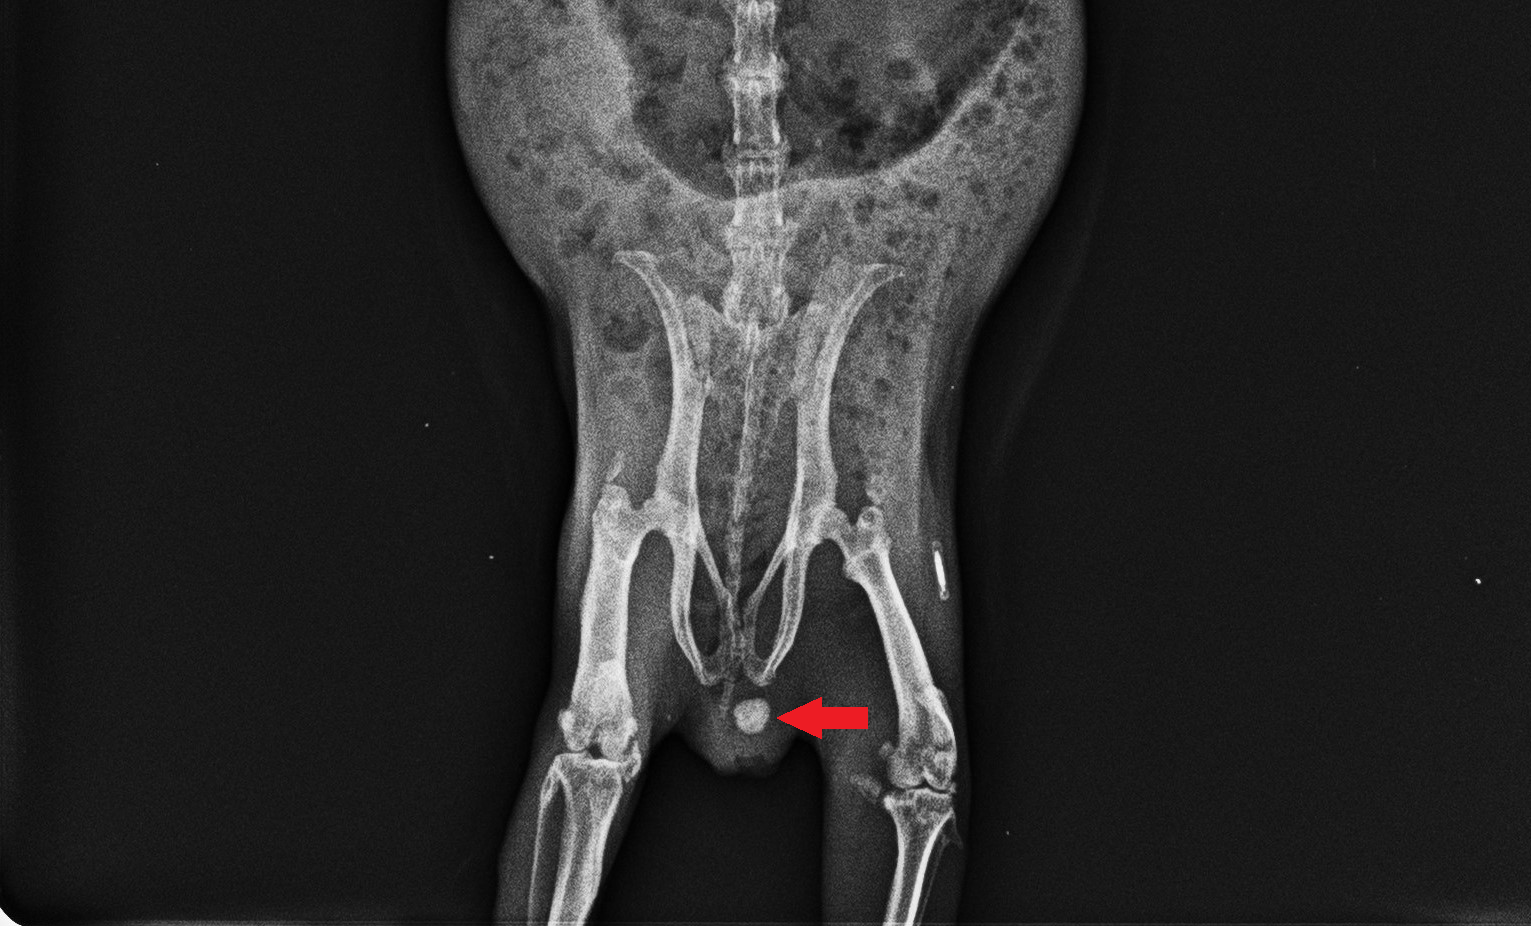

レントゲンでも映ることがあり、こちらの赤矢印で示した、白く丸いものが尿石です。(向かって右にある白く細長いものはマイクロチップです。)

尿結石は、腎盂、尿管、膀胱、尿道などの尿路系で認められる結石のことをいいますが、モルモットではまれにメスでは膣、オスでは精嚢腺内といった場所にも結石がみられることがあります。遺伝やカルシウム過多の食餌、飲水量の不足、細菌感染などが原因で発生するといわれています。